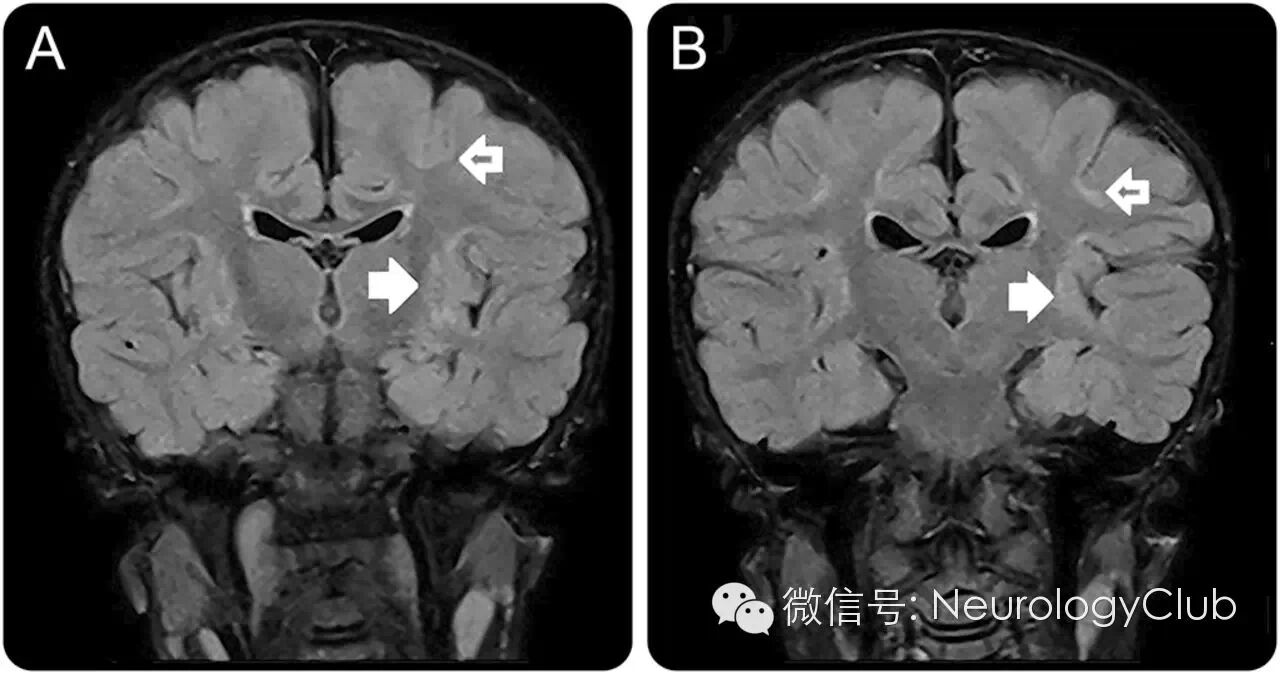

病例2

41岁患者,女性。

(T2/FLAIR提示双侧小脑深部白质[齿状核]及基底节区[苍白球]对称性高信号)